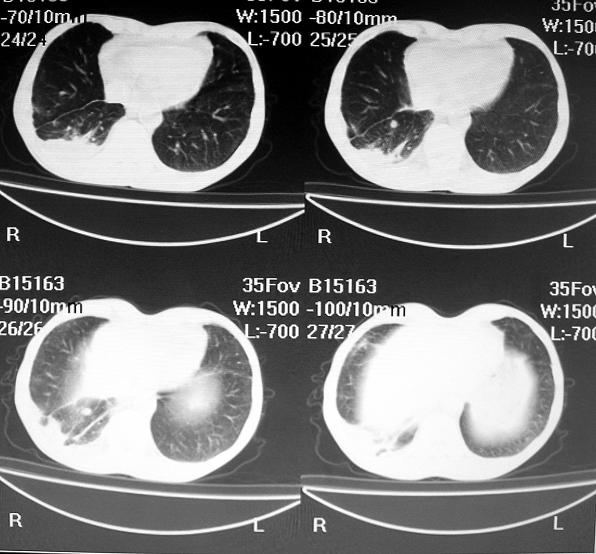

标题: CT10688:男63岁胸痛来诊 [打印本页]

标题: CT10688:男63岁胸痛来诊

男63岁胸痛来诊

右下肺周围性肺ca并双肺及右侧胸膜转移。[emb6]

右肺病灶前缘不平整,略呈分叶状,其后方胸膜下脂线消失且似有向胸壁浸犯,左下肺球形灶内可见不规则空洞影,余双肺内可见多枚结节影,结合病史支持考虑肺癌肺内转移胸膜转移,便双肺后部病灶倒也是结核好发区域,建议穿刺活检

[quote]以下是引用余辉在2007-12-2 20:29:00的发言:[br]右肺病灶前缘不平整,略呈分叶状,其后方胸膜下脂线消失且似有向胸壁浸犯,左下肺球形灶内可见不规则空洞影,余双肺内可见多枚结节影,结合病史支持考虑肺癌肺内转移胸膜转移。

支持!警惕韦格氏肉芽肿。

左肺病灶内可见空泡征及典型的胸膜牵拉征,不排除原发周围型肺癌的可能.